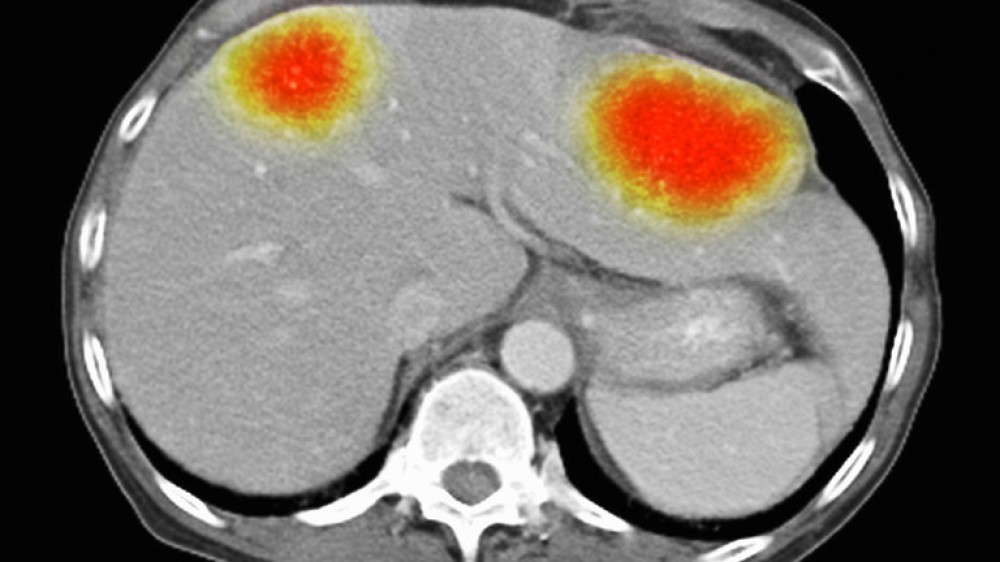

ويعد الورم الدبقي من أكثر أنواع السرطان عدوانية وصعوبة في العلاج. ويبلغ معدل البقاء على قيد الحياة لمدة خمس سنوات 6.8% فقط. ويقدر متوسط البقاء على قيد الحياة للمرضى بثمانية أشهر فقط بعد التشخيص. وتنتشر بعض الأنواع بشكل خاص عند الشباب.

ووجد فريق نوتنغهام أنه عند استهداف خلايا الورم الأرومي الدبقي بتقنية bio-antenna، تُركت الخلايا السليمة المحيطة بالسرطان دون مساس.